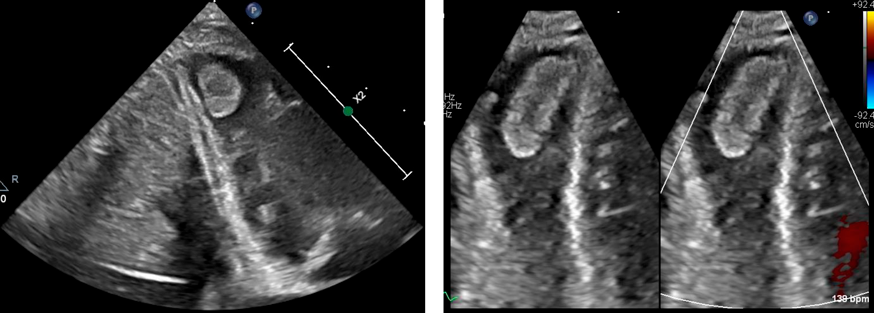

胸部レントゲン(Fig. 1A)でCTR 68%,肺うっ血を認めたが胸水はなかった.血液検査(Table 1)でWBC 11,600/µL(Neut 30.5%, Eosin 2.5%, Lymph 62%),好酸球数290/µL, AST 118 U/L, ALT 138 U/L, CK 1,618 U/L, CK-MB 190.4 U/L, CRP 0.26 mg/dL, Troponin T 0.398 ng/mLと心筋逸脱酵素が上昇していた.12誘導心電図(Fig. 1B)ではHR 150/分,V1からV6誘導で陰性Tであった.またlongRPのため心房性不整脈による頻拍誘発性心筋症を鑑別するためATP(1.5 mg–2.5 mg–2.5 mg)を投与したが反応はなかった.急性心筋炎と判断し入院とした.

Fig. 1 Chest X-ray and twelve-lead ECG on admission

(A) Chest X-ray on admission shows a pulmonary vascular congestion with a cardiomegaly. (B) Twelve-lead ECG on admission reveals tachycardia and long RP. Negative T waves are shown on V1 to V6.